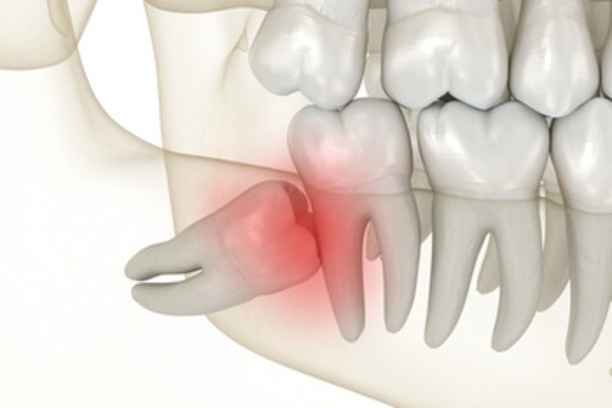

في أي الحالات يتم خلع ضرس العقل؟

توجد حالات محددة يصبح فيها خلع ضرس العقل خيارًا ضروريًا، ومنها:

• بزوغ الضرس بشكل مائل أو أفقي يضغط على الأسنان المجاورة.

• التهابات متكررة في اللثة لا تستجيب للعلاج الدوائي.

• تسوس عميق في الضرس يصعب ترميمه بسبب موقعه.

• تكون أكياس أو أورام حميدة حول جذر الضرس.

• ازدحام الأسنان وتأثير الضرس على انتظام التقويم.

• آلام مزمنة لا يمكن التحكم بها بالمسكنات التقليدية.

في مثل هذه السيناريوهات، تصبح اعراض ضرس العقل مؤشرًا واضحًا على ضرورة التدخل الجراحي لتفادي مضاعفات أكبر.